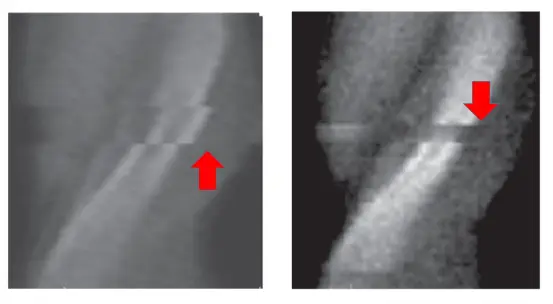

- 影像特徵:圖中展示的是 PET 的弦波圖(Sinogram)。弦波圖的 X 軸代表徑向距離(Radial distance),Y 軸通常代表投影角度(Projection angle)或掃描時間。

- 正常表現:在正常且病患完全靜止的掃描中,視野內的放射性分布(如器官或病灶)在弦波圖上會呈現連續且平滑的正弦曲線(Sine wave)亮帶。

- 異常發現:紅色箭頭明確指出亮帶出現了突兀的「水平不連續平移」與「斷層」現象。這代表在特定的掃描時間點(對應 Y 軸的某一位置),發射出互毀輻射(Annihilation radiation)的射源位置在 X 軸(空間位置)上發生了瞬間的位移。